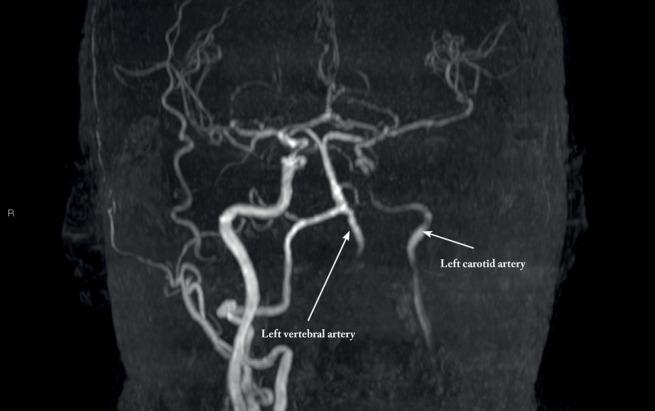

We present a case of 51-year-old female patient who was admitted at the Clinic of Nephrology and Clinical Immunology. During hospitalization, a sudden onset of intense chest pain occurred, followed by a development of heart failure to the level of cardiogenic shock. Electrocardiography showed signs of ST-elevated myocardial infarction (STEMI) of the anterior wall, and an increase in cardiospecific enzymes. CT angiography indicated an occlusion of the left common carotid artery (ACC), subclavian and axillary arteries as well as a penetrating aortic ulcer localized infrarenal. In the further course of treatment, left-sided weakness of the body was registered. Head CT scan showed an acute ischemic lesion high parietal on the right, as well as a chronic ischemic lesion on the front right. Doppler ultrasonography of carotid and vertebral arteries registered left occlusion, right ACC/external carotid artery (ACE) stenosis with suspected "macaroni sign". Final diagnosis of Takayasu arteritis was established and corticosteroids were included in the therapy (primarily in pulse doses) with the first pulse of cyclophosphamide of 1000mg.

我们报告一例51岁女性患者,她入住了肾脏病与临床免疫学诊所。住院期间,突然出现剧烈胸痛,随后发展为心力衰竭,达到心源性休克程度。心电图显示前壁ST段抬高型心肌梗死(STEMI)迹象,心肌特异性酶升高。CT血管造影显示左颈总动脉(ACC)、锁骨下动脉和腋动脉闭塞,以及肾下型穿透性主动脉溃疡。在进一步治疗过程中,发现身体左侧无力。头部CT扫描显示右侧顶叶上部有急性缺血性病变,右侧额叶有慢性缺血性病变。颈动脉和椎动脉多普勒超声检查显示左侧闭塞,右侧ACC/颈外动脉(ACE)狭窄,疑似“通心粉征”。最终确诊为高安动脉炎,并在治疗中使用了皮质类固醇(主要是脉冲剂量),首次给予环磷酰胺1000mg脉冲治疗。